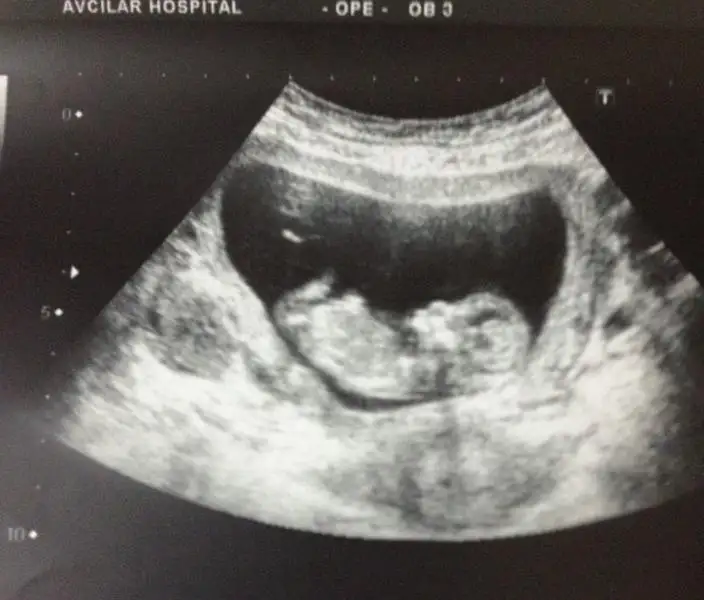

arkadaşlar bu ultrasyon resmide ablama ait ablam şuan 19 haftalık hamile ama dr lar hala net birşey diyemiyorlar belki siz bişiler dersiniz.

$bebeke4.webp $bebeke3.webp $bebeke1.webp $bebeke2.webp

kızlar ne olur cevaplayın=))